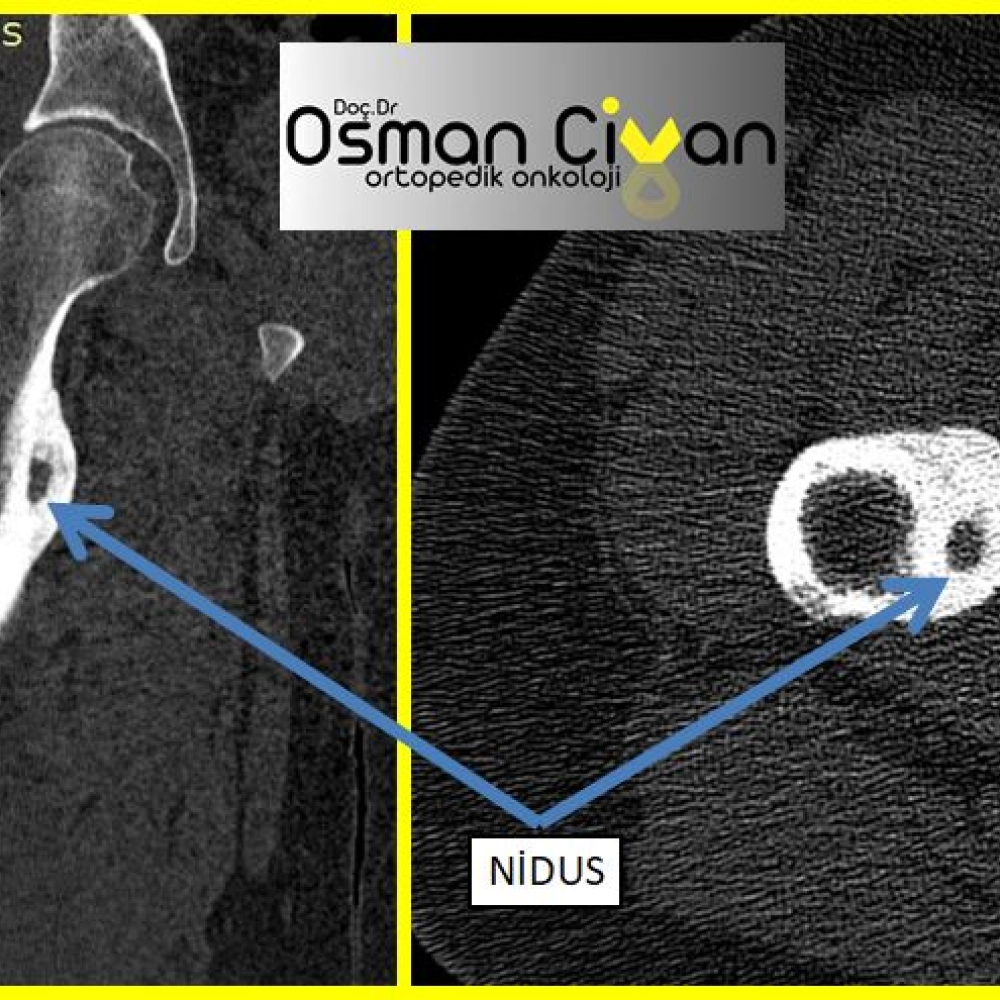

Osteoid Osteoma Nedir? Genellikle genç erişkinlerde ve çocuklarda görülen iyi huylu kemik tümörlerinden...